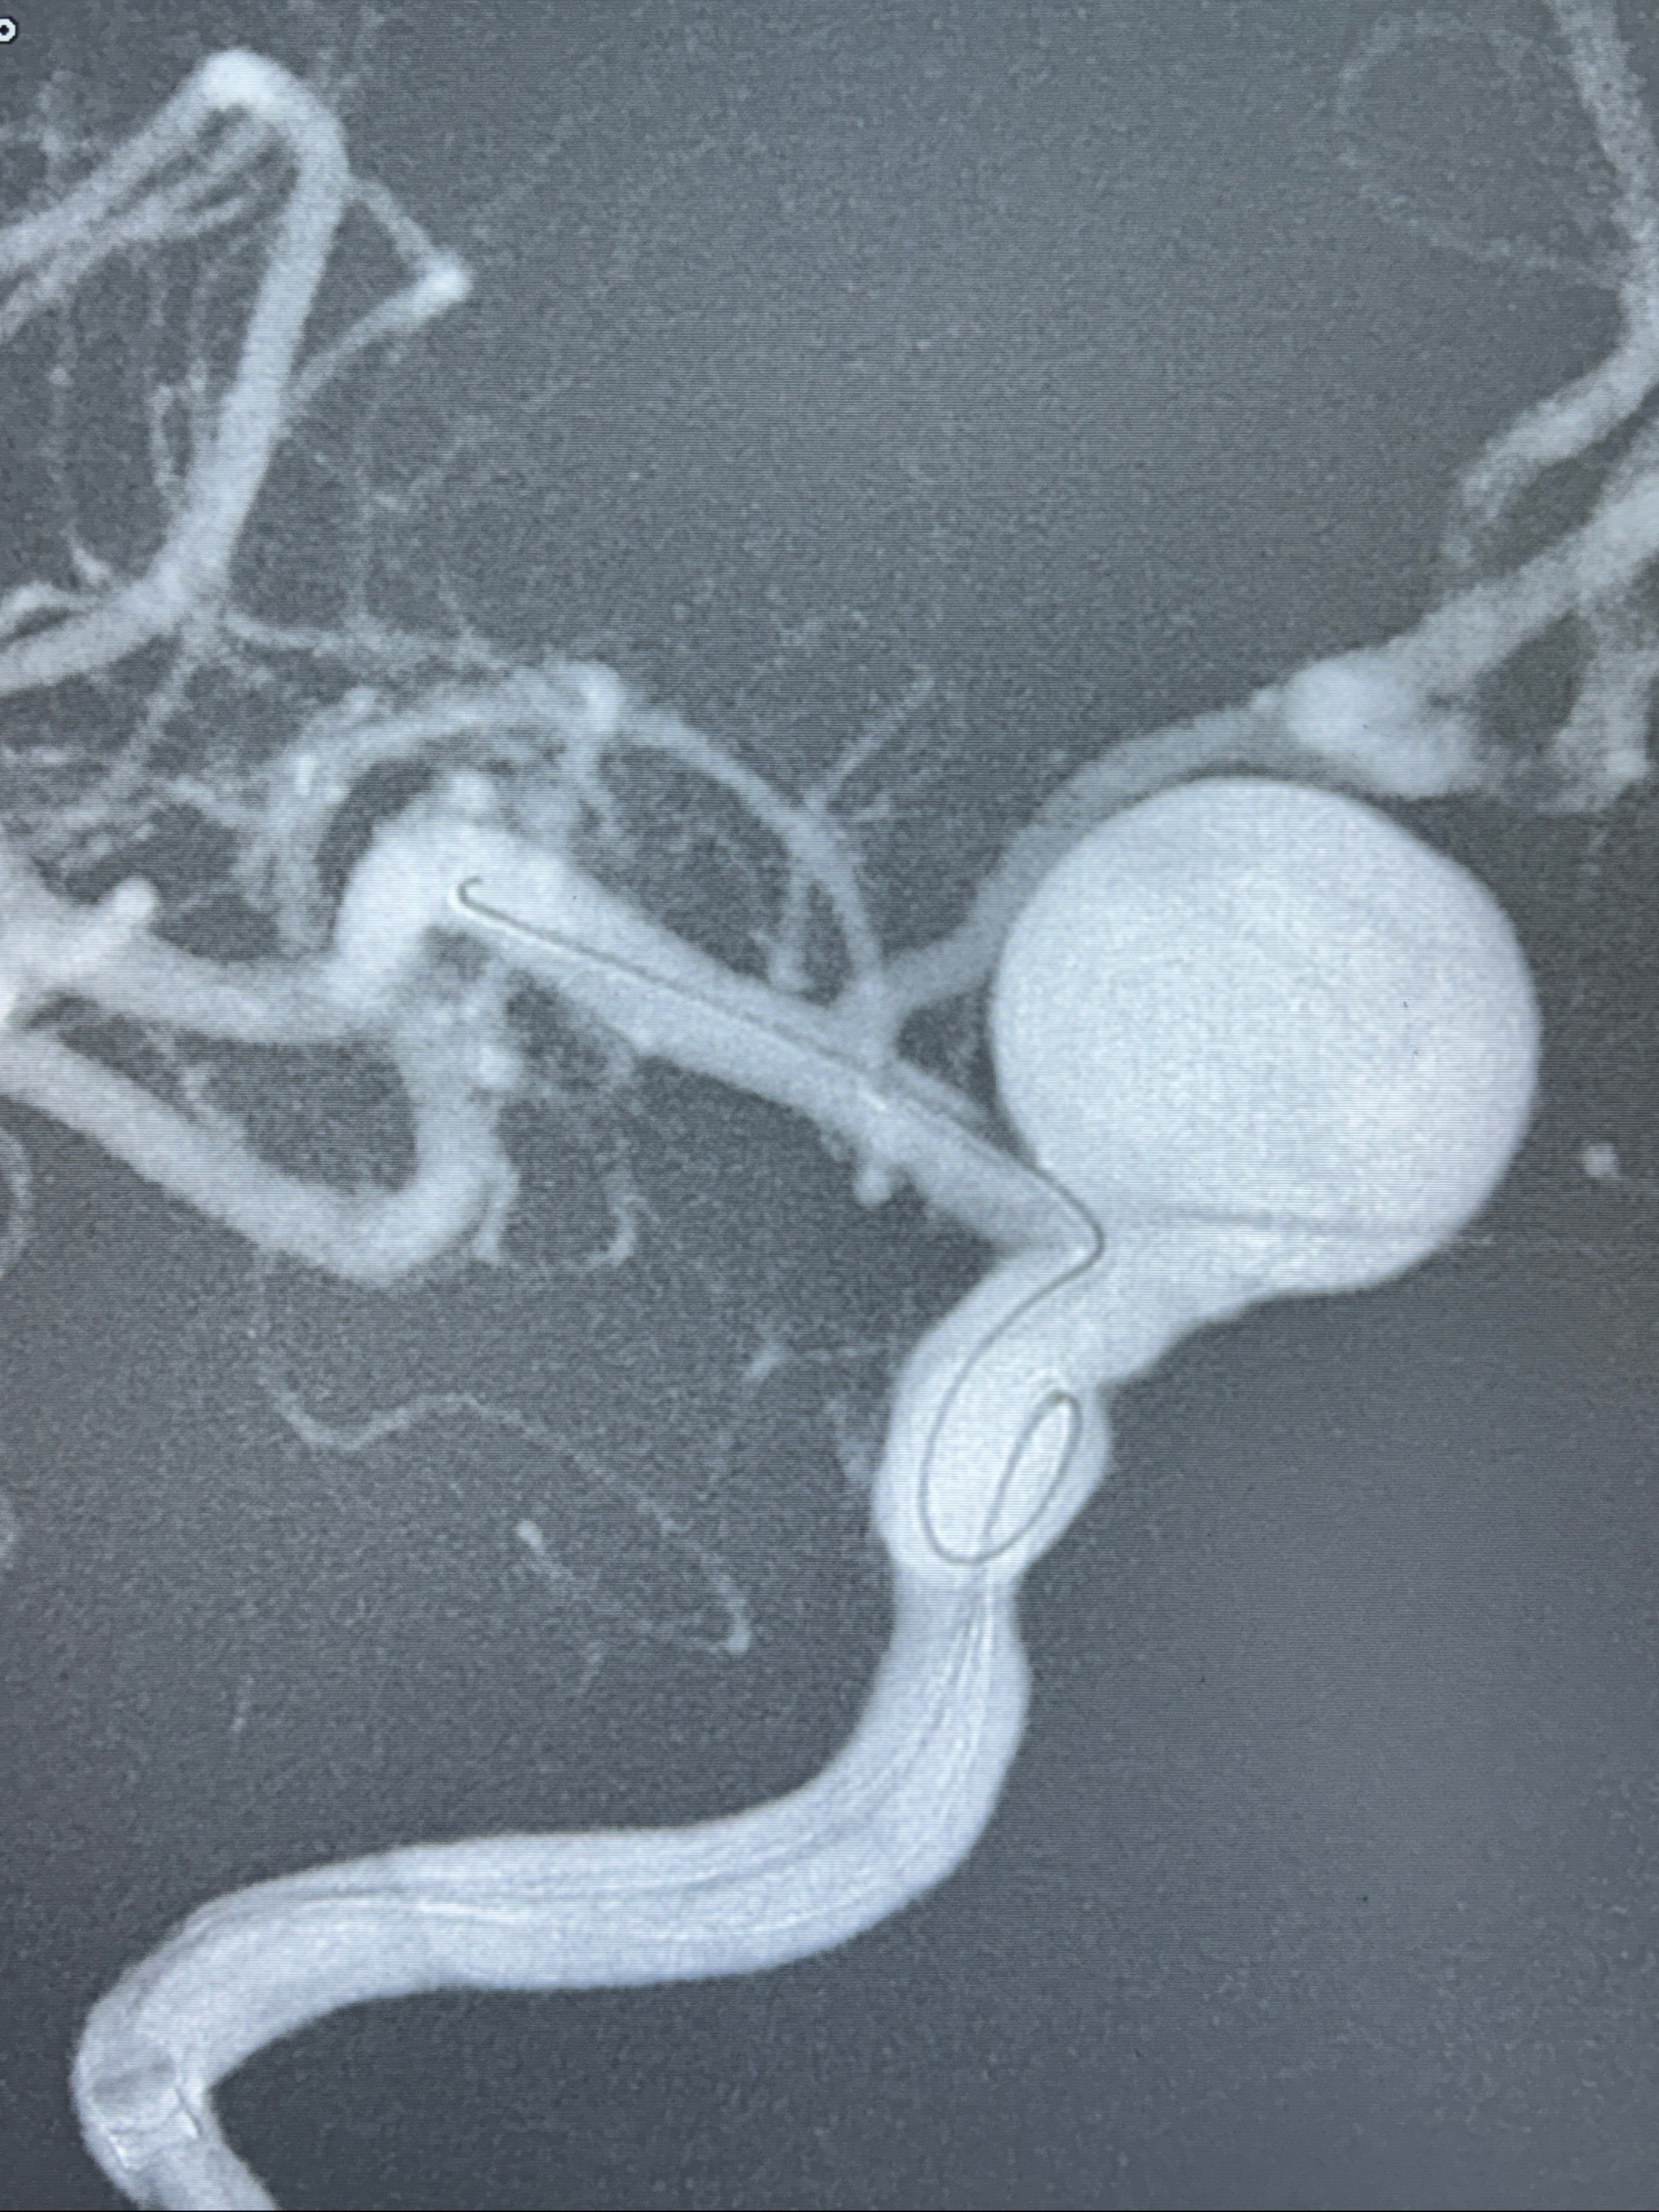

2023-12-27术后第十天复查DSA

支架贴壁佳,但可见射流,咋办?

2024-01-08全麻下再行植入密网支架一枚

Tubridge 4.5-35mm

支架植入顺利,贴壁佳,支架内血流通畅,动脉瘤内血液滞留明显